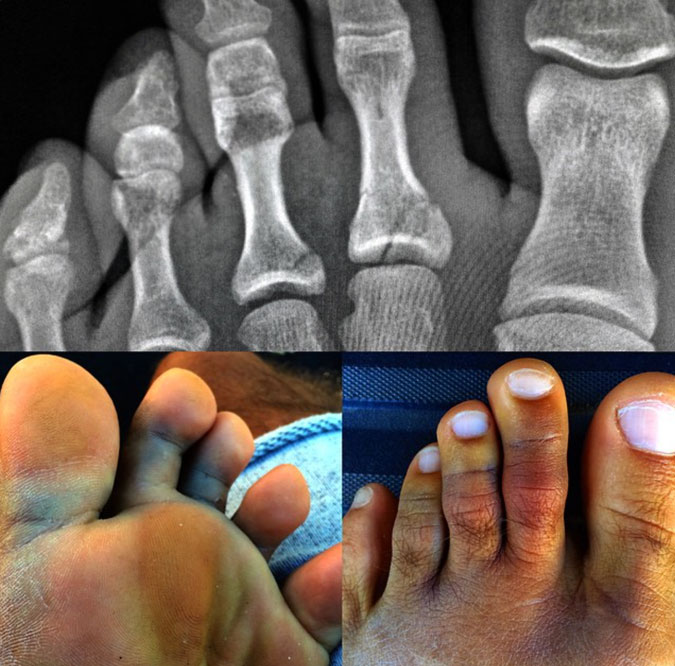

A solo un mes de Billabong Pipe Line Master, quelly Slater sufre una lesión en dos de sus dedos de un pié. ël dice que no se quedará sin disputar esta final así que está trabajndo para recuperarse de su lesión producida por una sesión de surf en Cloudbreak. Ahora esto no es nuevo para Kelly Slater ya que para los que han visto el video Blue Horizon de Jack McCoy pueden recordar la final en Teahupoo donde Kelly Slater gana justamente con los dedo rotos de su pié ese evento además asegura que se recuperará para ver si se adjudica nuevamente otra estrella y bate otro record mundial.